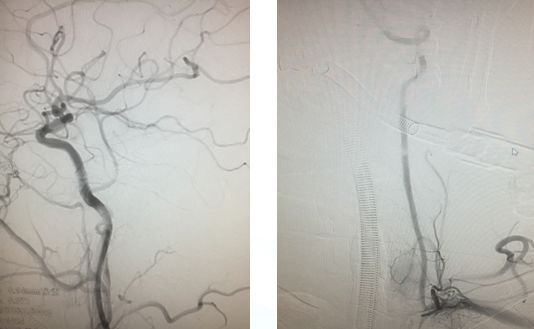

造影示:颈内动脉闭塞,眼动脉有代偿,血管闭塞原因决定血管再通方式!

找到闭塞血管部位,狭窄?夹层?

在颈内远端用6*30Solitaire逐次向近端释放支架(夹层可能性大)

支架释放状态血管通畅,逐渐找到血管闭塞部位

支架在病变最近端释放

11-3,21:40:血管再通,支架释放解脱